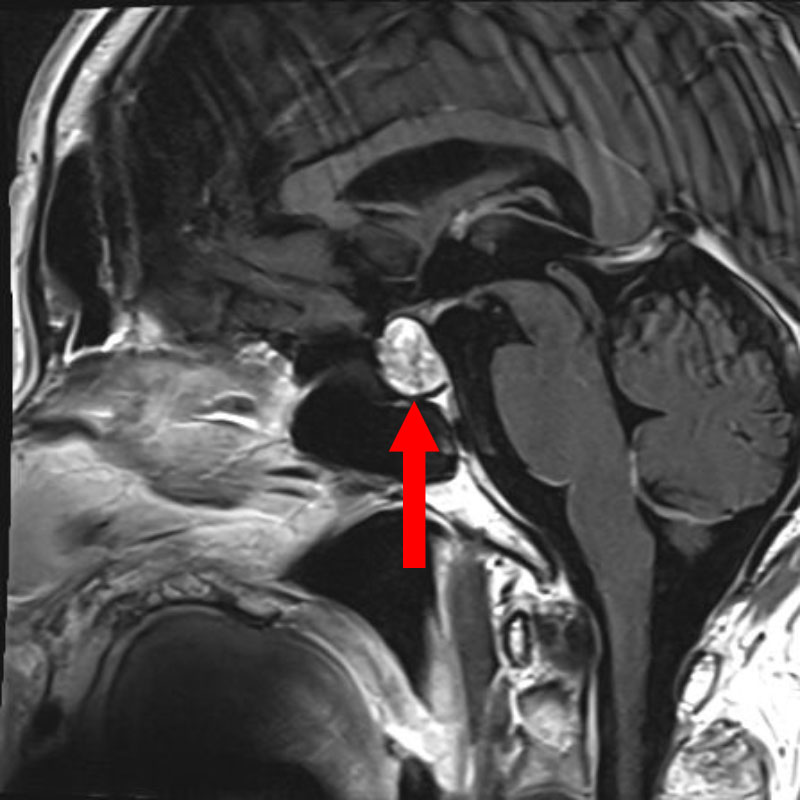

No.’25_74 手術前1

No.’25_74 手術前2